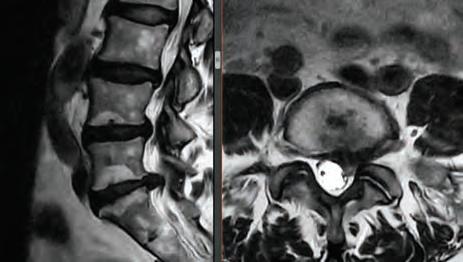

Stephen P. Courtney, MD

For board-certifid, fellowship trained orthopedic spine surgeon

Dr. Stephen P. Courtney, patients come fist. It’s an ethos that developed early on in his life and one that has helped guide him in his journey to earn a distinguished reputation among his professional colleagues, medical peers and, most importantly, his patients.

Led by Dr. Courtney, the skilled team at Advanced Spine Center cares for patients with neck and back pain using a wide array of the most state-of-the-art tools and techniques—from conservative physical therapy and injection therapy—to advanced pain manage-

SPINE SURGEON PRACTICING FOR 28 YEARS.

ment, as well as surgical intervention. We employ the latest in minimally invasive spine surgeries, in addition to cutting-edge replacement technology. Incorporating both high tech and high touch, we get our valued patients back to their lives so they can enjoy all the activities they love.

SURGERY: L5/S1 360° LUMBAR FUSION

SURGERY: LEFT L5/S1 MICRODISCECTOMY

SURGERY: C4/C5, C5/C6, C6/C7 ACF (ANTERIOR CERVICAL FUSION)

SURGERY: L4/5, L5/S1 360° LUMBAR FUSION